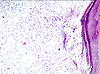

CASO N° 4 (Dr. Bonan e Dr. Roman)

Paciente do gênero masculino, 46 anos de idade, apresenta lesão no palato.